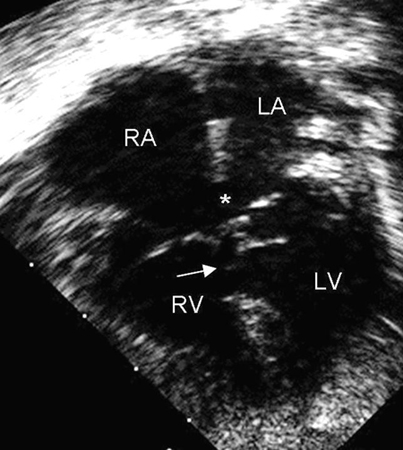

Representa 4% a 5% de todas as CCs e é encontrado em 40% das crianças com síndrome de Down.[32] Esse defeito também é chamado de defeito do coxim endocárdico ou defeito do canal atrioventricular (AV). Os coxins endocárdicos fecham o ostium primum e formam porções das valvas AVs e do septo ventricular. Os DSAVs podem ser parciais ou completos; um tipo de DSAV parcial é um defeito do septo atrial (DSA) primum. Um DSAV completo consiste em um DSA primum e um defeito do septo ventricular (DSV) de entrada contígua.[Figure caption and citation for the preceding image starts]: Imagem da ecografia apical de 4 câmaras de um defeito do septo atrioventricular (DSAV) completo. Note o ostium primum no defeito do septo atrial (DSA) (*) e o defeito do septo ventricular (DSV) de entrada adjacente (seta). (AD) átrio direito; (AE) átrio esquerdo; (VD) ventrículo direito; (VE) ventrículo esquerdoImagem cedida por Patrick W. O'Leary, MD [Citation ends].